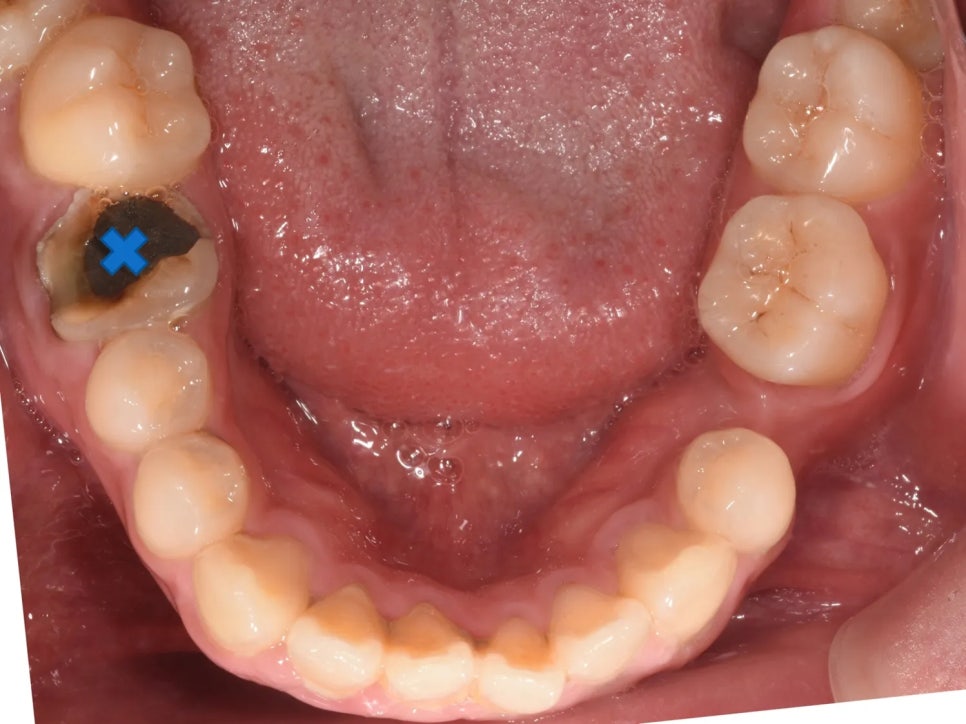

아래쪽 오른쪽에는 심한 충치, 반대쪽에는 이미 치아가 빠져 있는 상태

추가적으로, 아래쪽 오른쪽 첫째 어금니에는 심한 충치가 있었고, 반대쪽(왼쪽) 아래 두 번째 작은어금니는 이미 빠진 상태(결손)였습니다. 충치로 인해 치아 높이가 낮아지면서 위 어금니가 더 빨리 정출되었고, 결손 부위에서는 인접 치아가 빈 공간 쪽으로 쓰러져 있었습니다. 아래 사진을 보시면 이 모든 이유 때문에 결국 환자분이 아래턱을 틀어 물고 있는 것도 확인해보실 수 있습니다.

| 아래 오른쪽 첫째 어금니 | 충치가 너무 심해서 보존이 어려움. (통상 교정시 빼는 작은어금니 대신 발치.) |

아래 왼쪽은 이미 두 번째 작은어금니가 빠져 있기 때문에 추가 발치가 필요 없었습니다. 결과적으로 위 2개, 아래 1개 발치 + 기존 결손 1개 = 총 4개 공간을 활용하는 계획이었습니다.